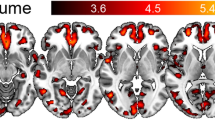

Comparison of deep and superficial white matter pathology and DWI variables in TLE. Pyramid graphical representation of DWI measures (top) and pathology factors which showed significant differences between the superficial and deep white matter (data shown is average scores across all core and deep white matter regions (superior, middle and inferior temporal gyri) and p values shown with Wilcoxon rank score test). AD = Axial Diffusivity, MD = Mean Diffusivity, RD = Radial Diffusivity, FA = Fractional Anisotropy, FIXEL = Fixel Based Analysis Measurement

DWI metrics in relation to white matter pathology

DWI measures showed regional differences in TLE with RD values higher in the gyral cores than deep white matter whereas AD, MD, FA and FDC were higher in the deep regions, using data from superior, middle and inferior temporal gyri (Fig. 3). Linear regression analysis of DWI values with pathology variables revealed greater significance in core than deep white matter regions (Supplemental Table 3). Glial labelling (Iba1 and PDGFRβ) increased with higher diffusion parameters (AD, RD and MD, p < 0.05 to < 0.0001) and higher myelin (PLP) labelling with lower AD (p < 0.05) and FA values in the core (Fig. 4A-D). Regarding vasculature, type 2 vessel density regressed with FA and FDC measures in the core white matter: higher PDGFRβ and SMA with lower FA and greater FDC, respectively (p < 0.05), Fig. 4E,F). In the deep white matter, greater mean PVS associated with lower FA (Fig. 4G). In addition COL4 vessel diameters positively correlated with MD and AD in both core and deep white matter (Fig. 4H,I). These observations suggest that although DWI differences noted between core and deep white matter may partly be explained by anatomical differences in axon bundle organisation, alterations of glial density and vascular structures in TLE further influence diffusion measures (Fig. 5G). In the ten cases with paired DWI and gene-expression data from deep white matter, positive association between myelination genes (MOG, MAG, MBP, PLLP) and FA and negative relationship with RD was noted (Supplemental Table 3).

Diffusion weighted MRI (DWI) and Fixel-based analysis (FBA) with pathology correlations. Linear regression analysis of DWI measures averaged across either all core or deep white matter regions (also regressed using Z scores relative to control DWI data, where shown) against pathology variables in same regions (as mean scores and Z scores compared to control cases); data is shown where significant regressions were identified on univariate analysis (See also supplemental Table 3): (A) Iba labelling and AD, MD, RD (core white matter), (B) Iba1 and MD (deep), (C) Phospholipid protein (PLP) and FA, AD (core), (D), PDGFRβ Labelling index (LI) and MD, RD (core), (E) PDGFRβ type 2 vascular density and FA (core), (F) SMA type 2 vascular density and Fixel (Core), (G) perivascular space measurement (PVS) and FA (Deep) (H) COL4 vascular diameter and AD and MD (Core) (I) COL4 vascular diameter and AD and MD (Deep). These confirmed the main associations for DWI and FBA with pathology were in the core white matter and for vascular pathology measures (see text for details). Pipeline for the DWI analysis: (J) Diffusion images following denoising, un-ringing, motion, eddy and field bias corrections were aligned to T1 and diffusions interpolated to match voxel size of T1 (1 mm). (K) Middle temporal gyrus (MTG) was rotated to align flat to enable orientation with brain slice, (L) Regions of interest (ROI) in white matter (superior temporal gyrus green shades, middle temporal gyrus blue shades, inferior temporal gyrus red shades with deeper colour shade representing deep ROI) were best matched and co-registered on MRI and pathology histological sections using Freesurfer white matter parcellation to manually segment gyri into the core and deep white matter (note the histology sections shown for illustration only or MRI and not aligned to MRI slice axis shown). (M) MRI images were then rotated back to extract diffusion tensors for each region. (N) Fixed-based-analysis (Left to right): 1. Individual orientation distribution function (ODF) were calculated, 2. registered to create a healthy population template, 3. which was used to create a SIFT filtered tractogram, for 4. Fixel-based analysis. RD = Radial Diffusivity, AD = Axial Diffusivity, MD = Mean Diffusivity, FA = Fractional Anisotropy, FIXEL = Fixel Based Analysis Measurement, LI = labelling index